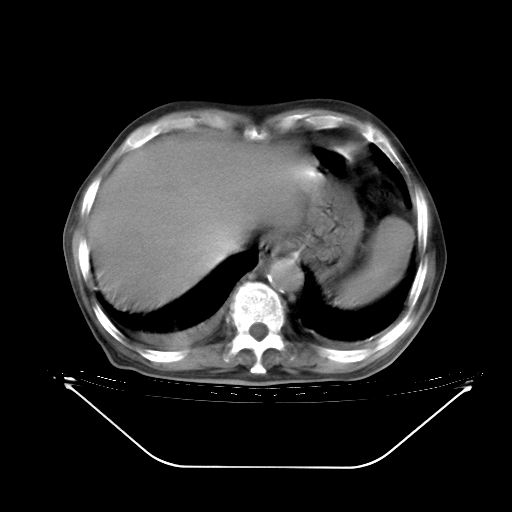

今天复查肺部CT,发现双肺广泛磨玻璃样改变。所以我把3月19日和5月9日相隔50天的肺部CT上传。请大家会诊。

2009年3月19日肺部CT片。

5月9日肺部CT(在4月27日齐鲁医院肺部CT描述部分肺组织磨玻璃样改变,12天后肺组织广泛磨玻璃样改变)